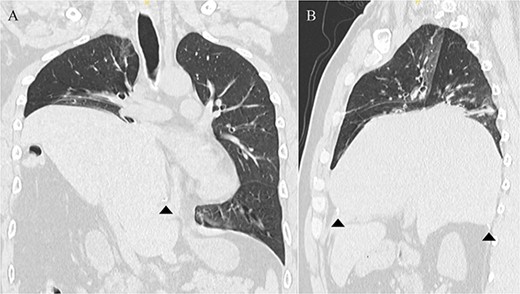

A 41-year-old man was referred to our hospital because of chest pain. Chest computed tomography (CT) revealed an anterior mediastinal tumor, and it was resected by median sternotomy. Pathological diagnosis was thymic cyst. Postoperatively, the patient developed right phrenic nerve palsy due to intraoperative stretch of the nerve and dyspnea on effort. After a year, the phrenic nerve palsy didn’t improve. He then underwent diaphragmatic plication by a right mini-thoracotomy. The elevated diaphragm was resected using an endostapler (Powered Echelon Flex®, black and green cartridges) without any reinforcement. After the second surgery, the surgical stump left by the endostapler ruptured, resulting in diaphragmatic rupture and defect. Chest CT revealed a large diaphragmatic defect (arrowhead) and prolapse of the liver into the thoracic cavity (Fig. 1). However, this condition had been misdiagnosed as the recurrence of diaphragmatic elevation for a year. His dyspnea increased in the supine position, and pulmonary function testing revealed restrictive ventilatory impairment, which led the correct diagnosis of diaphragmatic rupture. The vital capacity (VC) and %VC were 1.86 L and 39.8%, respectively. A year after the second surgery, we then repaired the diaphragmatic defect by right thoracotomy. The surgical view of the thoracic cavity showed that the liver had prolapsed from the large diaphragmatic defect, which measured 15 cm (Fig. 2). Severe adhesion was present between the liver and the edge of the torn diaphragm including the torn staple line and was carefully dissected. The diaphragmatic defect was closed with a 1 mm thick PTFE patch. Moreover, the diaphragm was reconstructed using a second 1 mm thick PTFE patch above the original placement, overlaying the diaphragmatic defect that had been closed by the first PTFE patch (Fig. 3, arrow). The second PTFE patch was fixed to the lower ribs by non-absorbable suture (Fig. 3, arrowhead). The operating time was 325 min, and the blood loss volume was 50 mL. The postoperative course was favorable, and the patient was discharged 7 days after surgery. Three months after the third surgery, his symptoms improved, and pulmonary function testing revealed that the VC and %VC were 2.24 L and 48.1%, respectively. Postoperative chest computed tomography revealed PTFE patch maintained a good position (Fig. 3).

Postoperative chest computed tomography showing the reconstructed diaphragm using a second polytetrafluoroethylene (PTFE) patch above the original placement, overlaying the diaphragmatic defect that had been closed by the first PTFE patch (arrow). The second PTFE patch was fixed to the lower ribs (arrowhead).